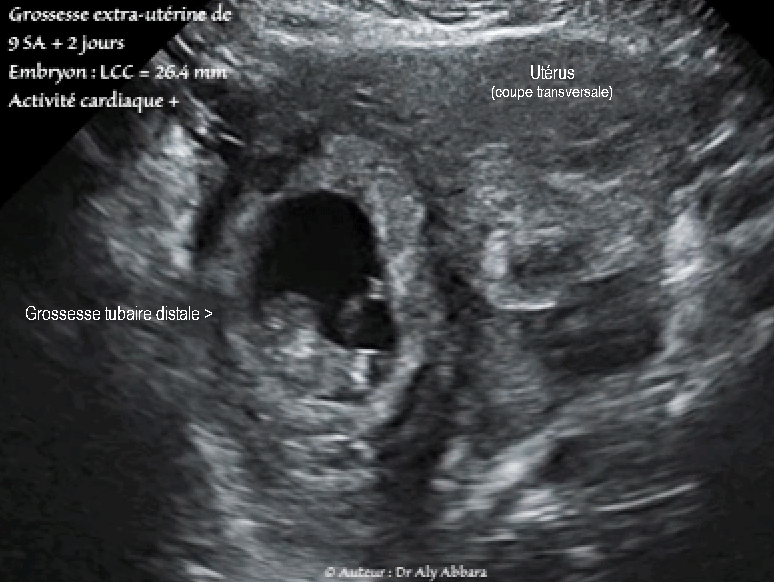

Grossesse extra-utérine tubaire distale évolutive âgée de 9 SA et 2 jours : activité cardiaque positive ; mouvements actifs positifs ; longueur craniocaudale égale à 26,4 mm - coupe transverse de l'utérus

• Séquences vidéos (type *.GIF) d'une exploration échographique par voie transpariétale (coupe transverse de l'utérus) mettant en évidence la présence d'une grossesse extra-utérine tubaire distale évolutive âgée de 9 SA et 2 jours :

• Sur d'autres coupes, on observe la présence d'un important épanchement intra-péritonéal atteignant l'espace de Morison. En per-opératoire, cette hémorragie intra-péritonéale a été évaluée à 1 300 ml.

Il s'agissait d'une grossesse extra-utérine tubaire droite en voie d'expulsion par un avortement tubo-abdominal.

• Ce sac gestationnel ectopique tubaire droit est associé à un tableau clinique caractérisé par la présence d'une douleur pelvienne intense et constante, sans métrorragie.

• Biologie : le dosage de β-hCG plasmatique était égal à 4 800 UI/l.